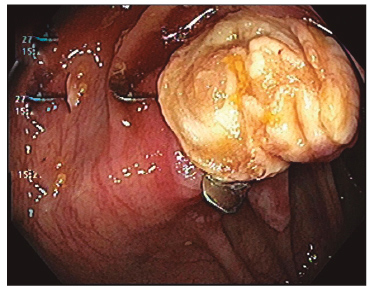

Un paciente masculino de 58 años presentó en la VCC, realizada por vigilancia de pólipos, una lesión elevada con una extensión lateral de tipo granular, de aproximadamente 40 mm con signo de levantamiento negativo (non-lifting sign) en el ángulo hepático (Figura 8 A). Ante esta evidencia de irresecabilidad endoscópica por técnicas convencionales, se indicó la EFTR (Figura 8 B).

La reinspección endoscópica no mostró signos de perforación ni de sangrado (Figura 9). El tiempo estimado del procedimiento fue de 55 minutos.

Luego de la resección, al evaluar la pieza extendida, se observó la marcación realizada de forma previa a la EFTR (Figura 10).

El examen anatomopatológico confirmó la resección transmural completa, en bloque, de un adenoma tubulovelloso con una displasia de alto grado y márgenes libres de lesión de 3,2 x 2 x 0,3 cm (Figura 11).